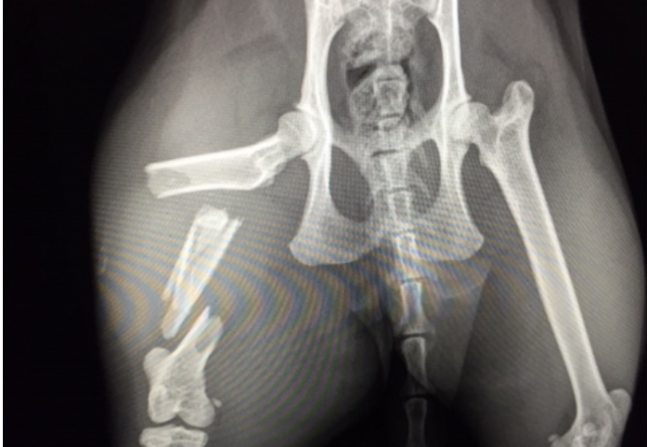

Bij bepaalde klachten is het maken van röntgenfoto’s een zeer nuttige vorm van aanvullend onderzoek en zullen ze bijdragen aan het stellen van de juiste diagnose. Röntgenfoto’s kunnen informatie geven over delen van het skelet maar ook over diverse organen.

Röntgenonderzoek is in sommige gevallen essentieel om een juiste diagnose en daardoor een optimale behandeling voor uw dier op te kunnen stellen. Door jarenlange ervaring is het maken en beoordelen van röntgenfoto’s bij WB Dierenartsen een vanzelfsprekendheid. Aan de hand van de uitkomst van het röntgenonderzoek kunnen we samen met u besluiten wat de volgende stap is. Mochten onze artsen aanvullende beeldvorming willen hebben, dan kunnen we nog een echo maken. In sommige gevallen zullen we u doorsturen naar een specialist voor een MRI of CT-scan.